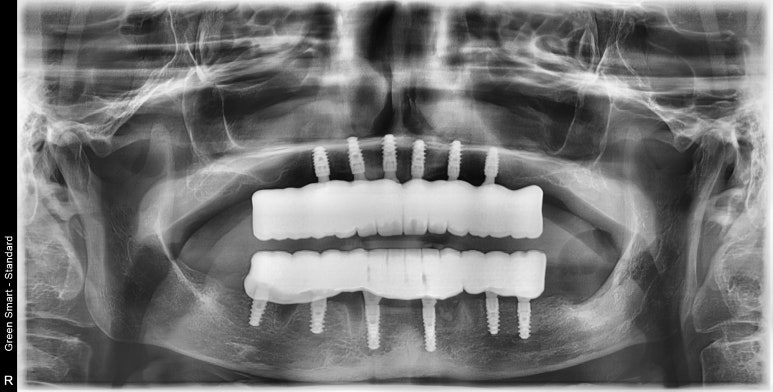

정리하는 의미에서 전후 사진을 비교해 보았답니다.

안모상 주름 개선, 젊어보이는 효과 부여를 관찰할 수 있답니다.

전후 비교/ 중심선을 잘 맞출수 있었답니다.

엑스레이 비교사진입니다.